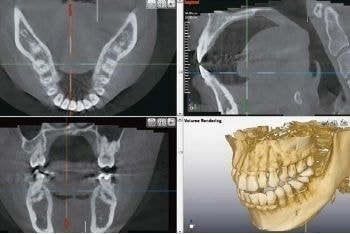

細部までしっかり診断

レントゲン装置には、レントゲン写真を3Ðで診断できるCTを採用し、歯の悪いところの診断も断面から診査出来ますので、平面で診査するよりも格段に悪いところを正確に把握することが可能となります。